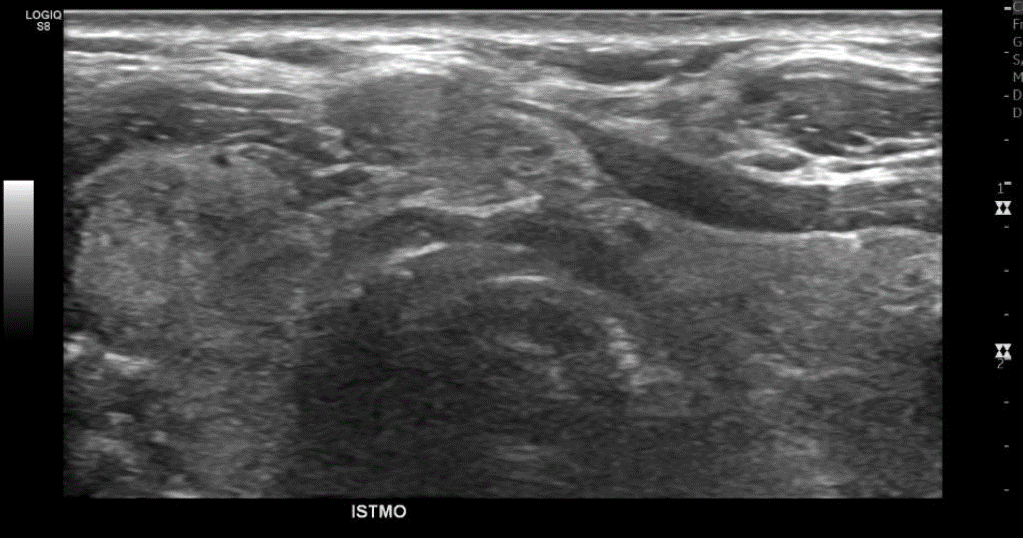

• Tiroides de parénquima heterogéneo, bordes irregulares, tamaño/vascularización conservada en LTI, no así LTD aumentado de tamaño/vascularización a expensas de los nódulos (3). → Bocio Multinodular

• Adenopatías de aspecto reactivo en Reg Cerv GI e Infra tiroideas peri-istmicas

Glándula tiroides de tamaño aumentado.

Presenta eco estructura interna heterogénea sin alteraciones del flujo vascular al estudio con Doppler-Color.

En el lóbulo tiroideo derecho lesión nodular ecogénica de 19 x 18 mm diámetro calcificada con sombra acústica posterior. Otra lesión nodular hipo ecogénica heterogénea en el polo inferior lóbulo derecho de 16 x 10 x 20 mm y otra de 11 x 11 x 10 mm, esta última con focos ecogénicos puntiformes sugerentes de calcificaciones. Adyacente al lóbulo derecho, lesión nodular hipo ecogénica heterogénea, de 27 x 60 x 23 mm, con focos ecogénicos sugerentes de calcificaciones. Glándulas submandibulares y parótidas de morfología normal. Linfonodos inespecífico en el grupo uno de 6 x 4 mm.

Impresión: Tiroides de tamaño aumentado con signos de tiroiditis crónica. Nódulos tiroideos bilaterales. Se recomienda complementar estudio histológico. TIRADS 5.